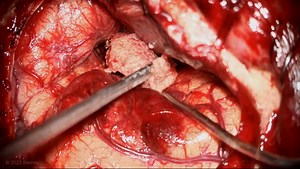

Surgery - Nasal Tumors

in Dogs - Sinus